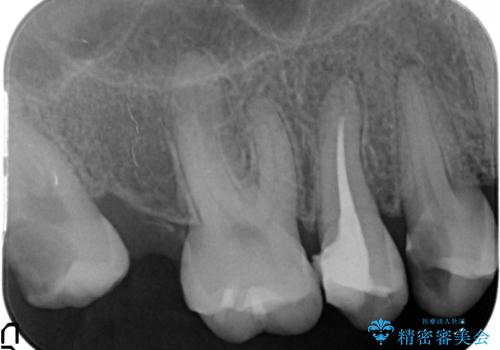

- 上下1本づつの歯を失い、噛めないことの改善を求めて来院されました。

保存可能な歯の虫歯・根管治療を行い、喪失した部分はインプラントを埋入、オールセラミックジルコニアクラウンを製作し審美的に仕上げていきます。

今回下顎の欠損部位はブリッジも検討されましたが、並行性の観点から最後方臼歯の神経を取るリスクを抑えるためインプラント治療を選択しました。